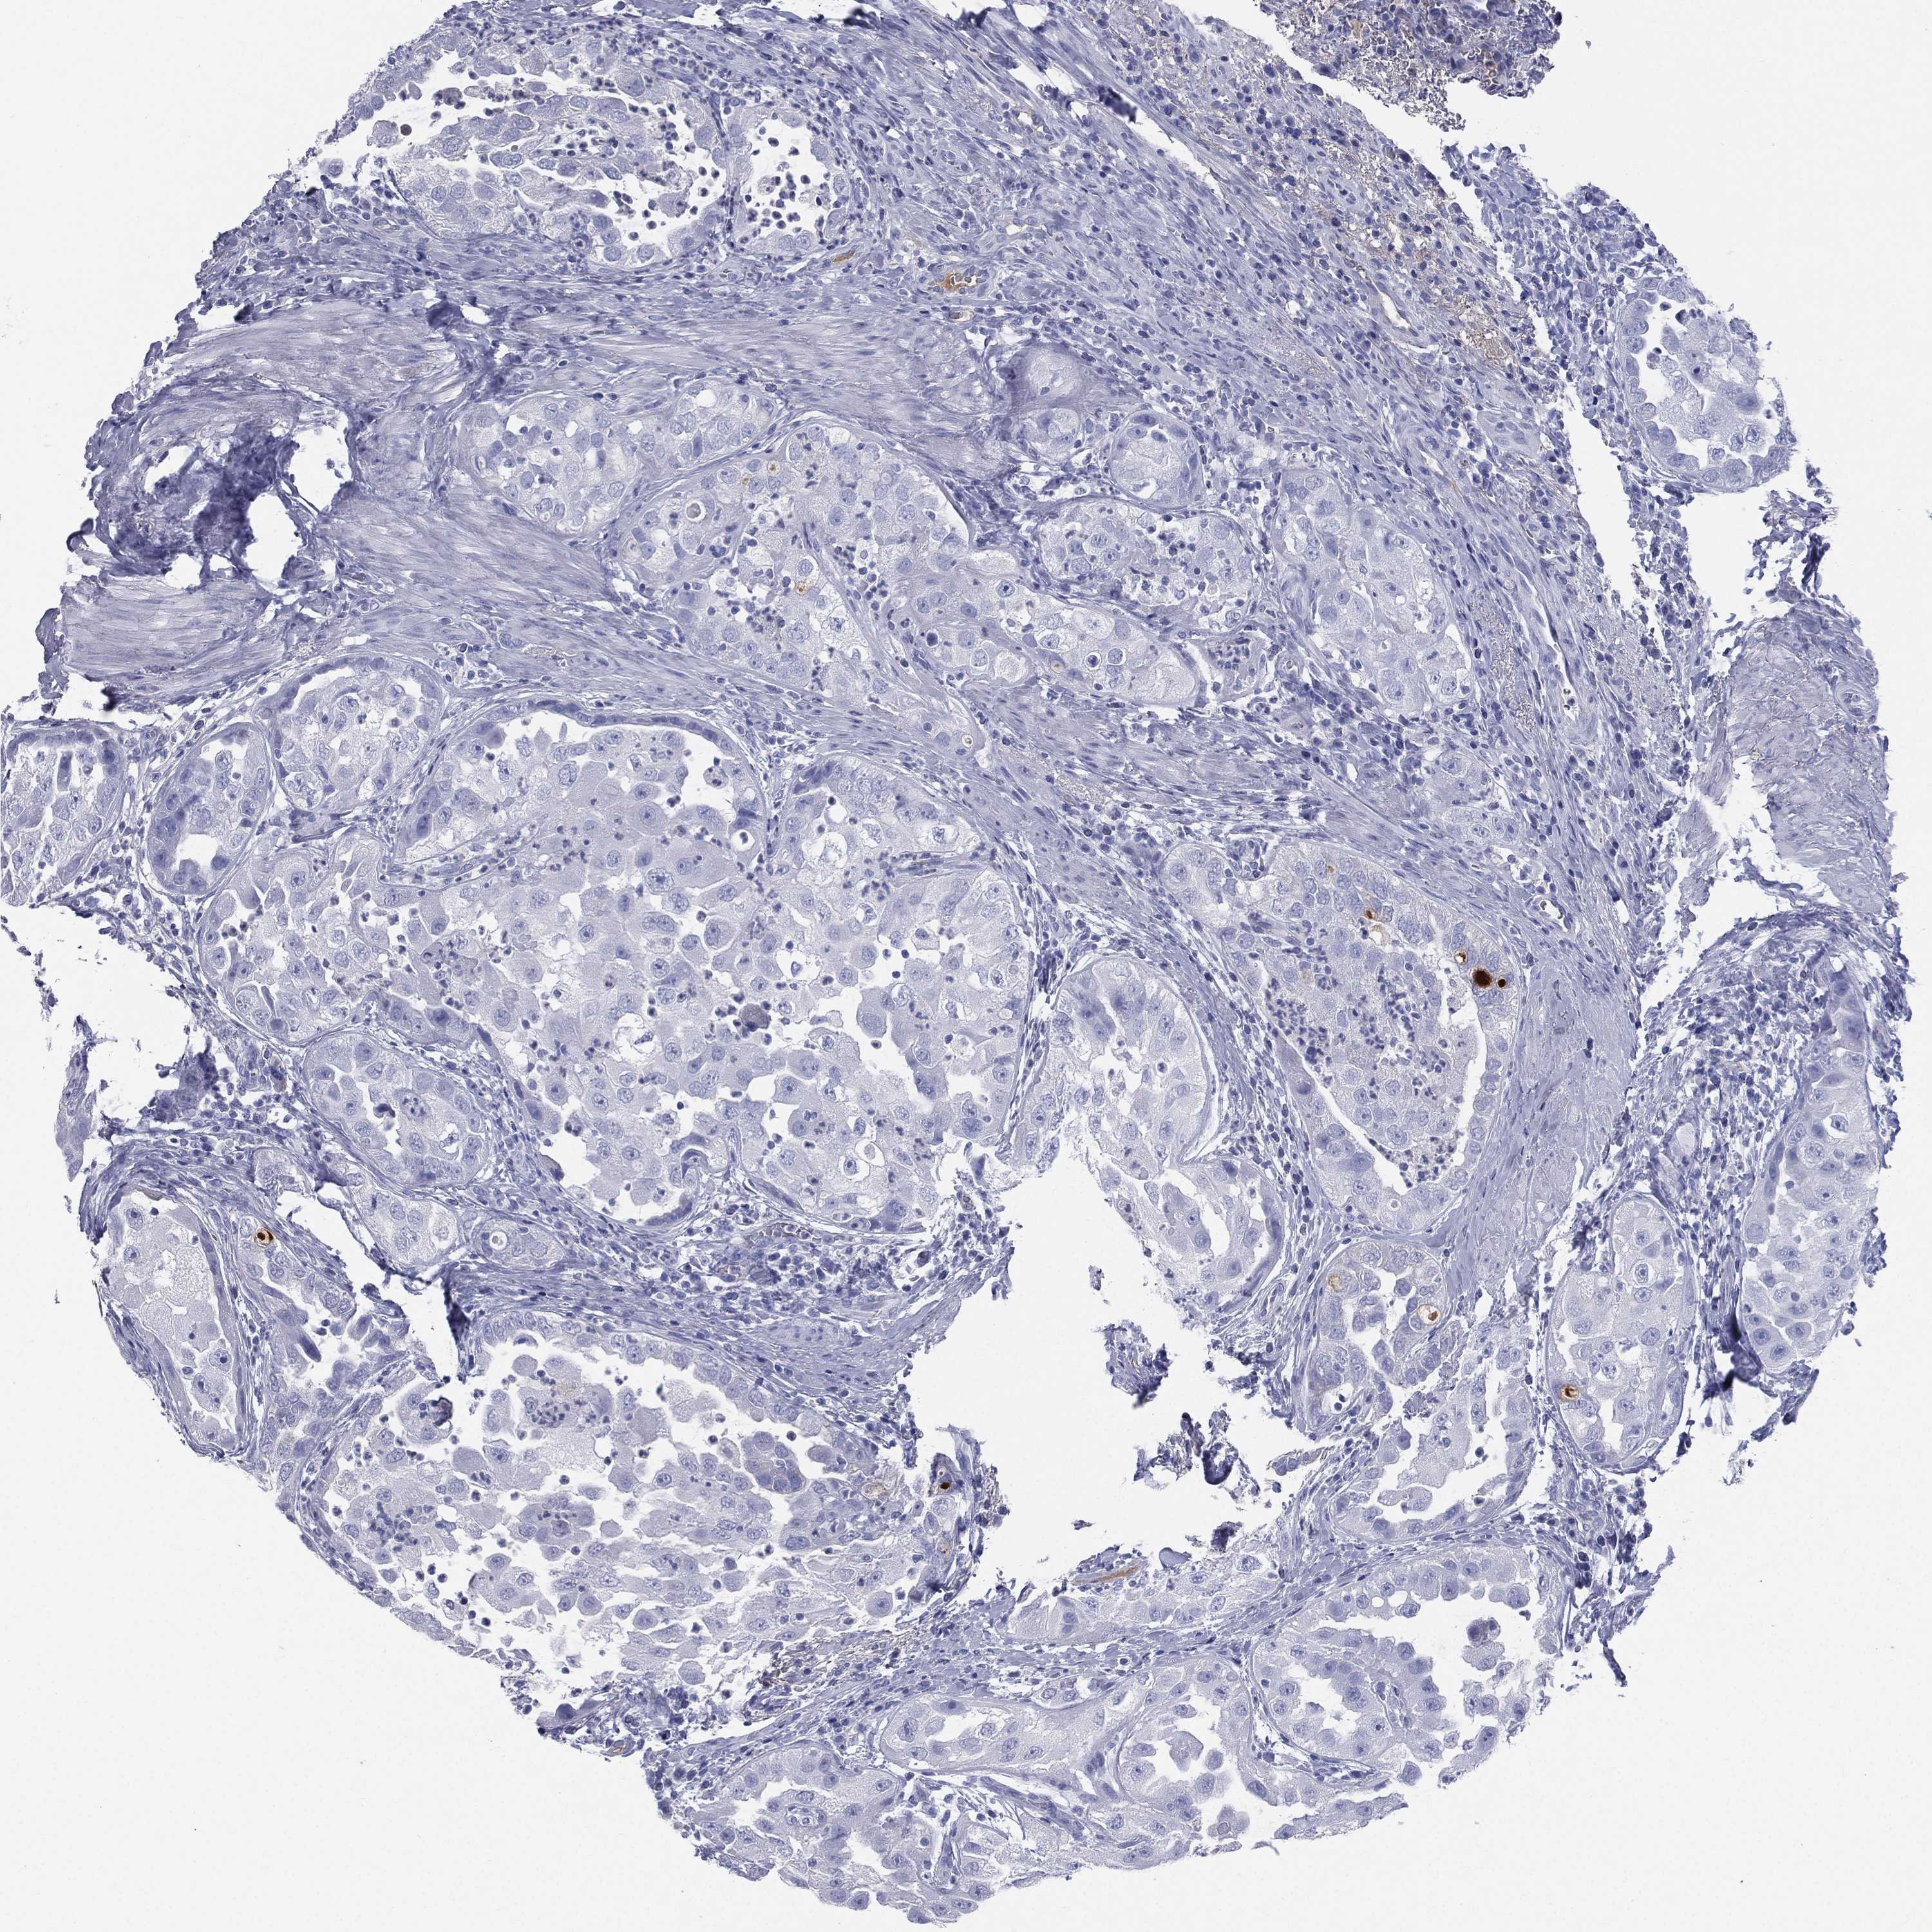

UROTHELIAL CANCER - Protein expressioni

A mouse-over function shows sample information and annotation data. Click on an image to view it in a full screen mode. Samples can be filtered based on level of antibody staining by selecting one or several of the following categories: high, medium, low and not detected. The assay and annotation is described here.

Note that samples used for immunohistochemistry by the Human Protein Atlas do not correspond to samples in the TCGA dataset.

Antibody stainingi

Antibody staining in the annotated cell types in the current human tissue is reported as not detected, low, medium, or high, based on conventional immunohistochemistry profiling in selected tissues. This score is based on the combination of the staining intensity and fraction of stained cells.

Each image is clickable and will lead to virtual microscopy that enables deeper exploration of all samples and also displays staining intensity scores, fraction scores and subcellular localization as well as patient and tissue information for each sample.

Antibody HPA047750

Antibody HPA066795

Antibody CAB003787

Urothelial carcinoma, High grade

Urothelial carcinoma, NOS

Urothelial carcinoma, Low grade